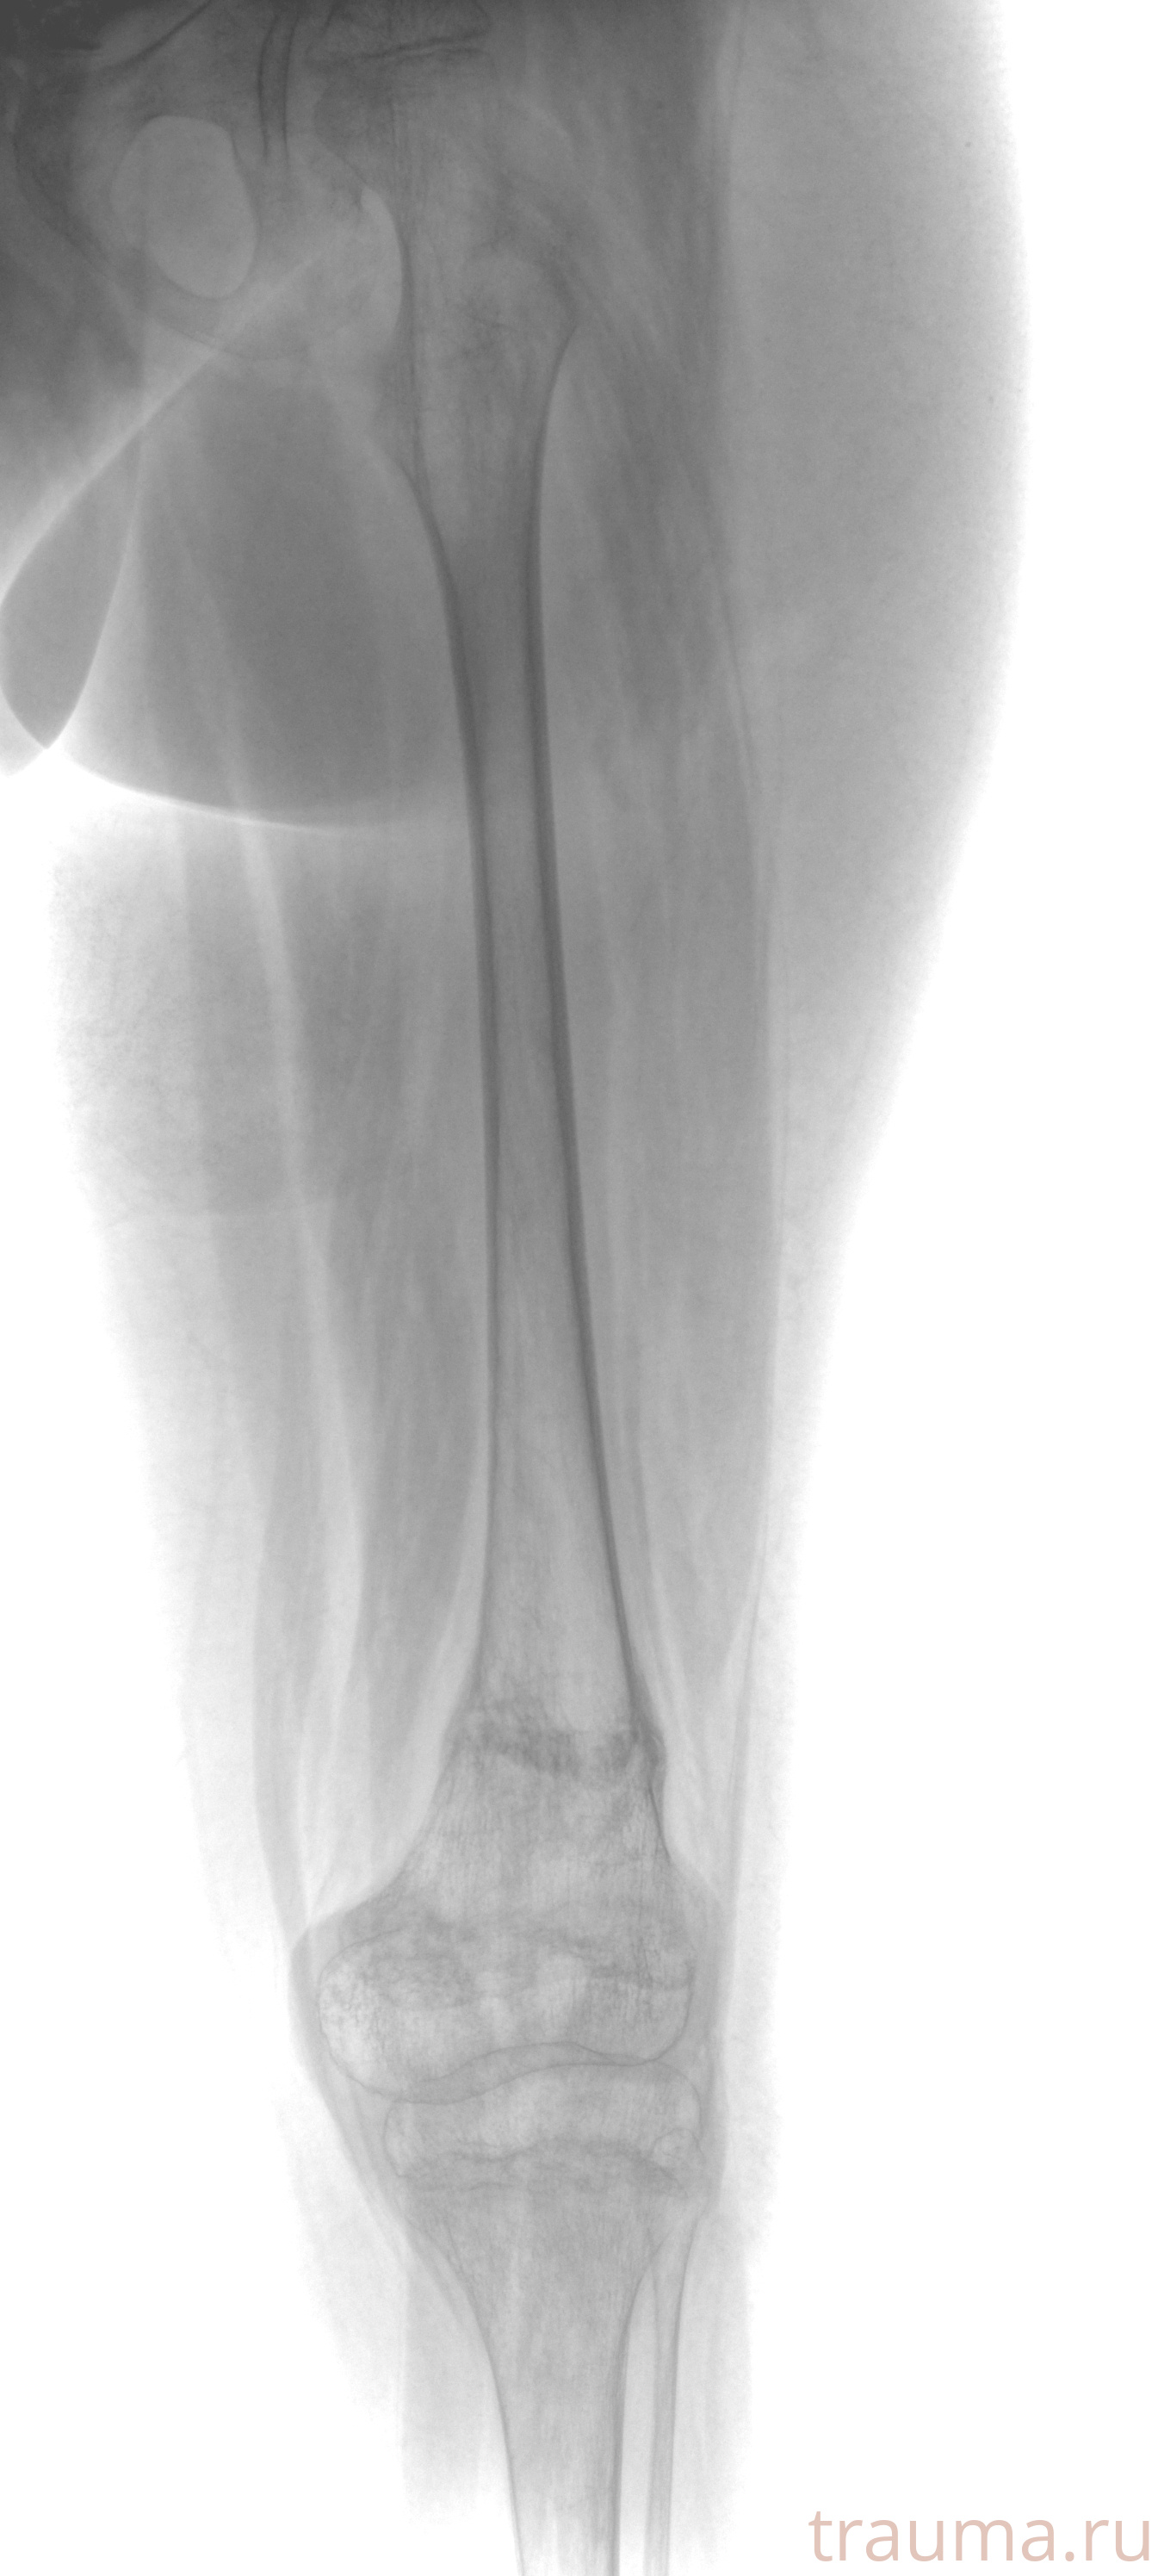

Рентген на дому: по вашему адресу приезжает врач-рентгенолог, травматолог-ортопед с мобильным рентгеновским аппаратом, проводит диагностику травмы или заболевания, делает необходимые рентгенограммы, дает рекомендации по дальнейшему лечению. Получить качественные снимки в домашних условиях возможно благодаря уникальной методике, разработанной МосРентген Центром для института  Склифосовского